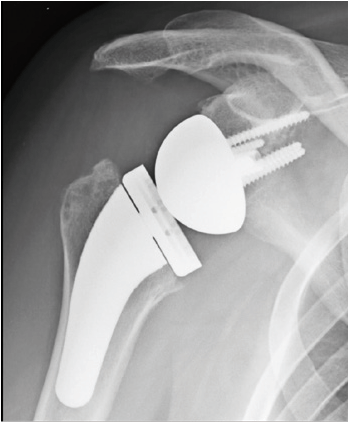

Inverse (umgekehrte) Schultergelenksendoprothese

Wenn diese Rotatorenmanschette verbraucht oder gerissen ist und zusätzlich eine Arthrose besteht, ist eine sogenannte inverse (umgekehrte) Schultergelenksendoprothese die Prothese der Wahl. Diese bietet gerade in derartigen Situationen vielversprechende Aussicht auf Schmerzfreiheit und eine gute Schulterfunktion.

Umgekehrte Prothese bedeutet, daß bei dieser Prothese der Kopf (Glenosphäre) auf der anatomischen Schulterpfanne verankert und die Pfanne im Bereich des ehemaligen Kopfes platziert wird - also gerade umgekehrt (=invers).

Dadurch wird der Drehpunkt des Schultergelenkes verlagert und ein anderer Hebelarm erreicht, dass der kräftige Schulterkappenmuskel (M. deltoideus) die Funktion der häufig nicht mehr vorhandenen Rotatorenmanschette übernehmen und ersetzten kann. Die inverse Schulterendoprothese bietet daher häufig in "verzweifelten Situationen" eine ausgezeichnete Behandlungsmöglichkeit. Im Fallbeispiel zeigt das Röntgenbild vor der Prothesenversorgung einen Zustand nach mehrfachen Operationen mit nach oben gerutschtem Oberarmkopf, Arthrose und Metallankern in der Pfanne. Die eingebaute inverse Prothese hat den Arm wieder nach unten gebracht, sodaß die Patientin den Arm nun wieder schmerzfrei nach oben heben kann ohne am Schulterdach zu reiben.